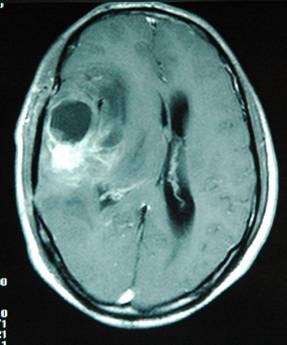

A previously healthy 45-year-old man presented with seizures and expressive aphasia. He was admitted to our hospital. Magnetic resonance imaging (MRI) documented a large contrast-enhancing lesion in the right temporal region (Fig. 1). The mass histological examination revealed a glioblastoma multiforme. About 10 years earlier the patient had suffered a cranial trauma in a road accident when he traveled in another city. After the trauma he had been unconscious for 3 days and CT scan demonstrated an intracranial hematoma in the right temporal lobe at the site of the subsequent glioblastoma. The intracranial hematoma was treated conservatively at that time. After the diagnosis of the glioblastoma multiforme the patient was treated with radiotherapy and chemotherapy, but he died seven months later.

Figure 1

MRI scan of the head show a large temporal mass secondary to the glioblastoma at the site of the previous intracerebral hematoma.